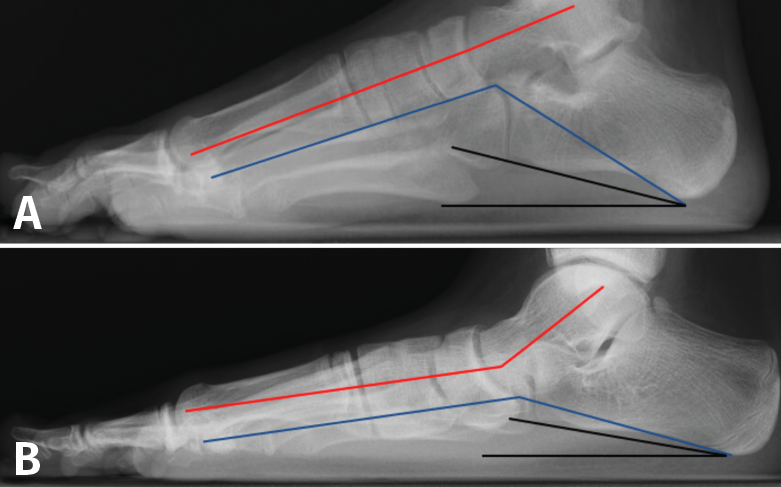

Radiografía lateral del pie en carga (Figura 6)

Figura 6. Radiografía lateral del pie en carga. A: pie normal; B: pie plano. Ángulo de Meary (rojo). Ángulo de Costa-Bartani (azul). Calcaneal pitch angle (negro).

- Ángulo de Costa-Bartani: mide el arco longitudinal medial y está definido por 2 líneas que unen respectivamente los puntos más bajos del calcáneo, el astrágalo y la cabeza del primer metatarsiano, siendo normal entre 125 y 135°. Aumentado en PPV, es una medida del aplanamiento del arco interno.

- Ángulo de Meary (ángulo lateral del astrágalo-primer metatarsiano): su valor normal es entre 0 y 10°. Este ángulo también es una medida del aplanamiento del arco interno y está alterado en los diferentes patrones de pie plano (media de 35°).

- Calcaneal pitch angle (ángulo de inclinación del calcáneo): es normal entre 20 y 30°. Está disminuido en todos los patrones de pie plano, excepto en el patrón de pie plano cavo, que está aumentado.